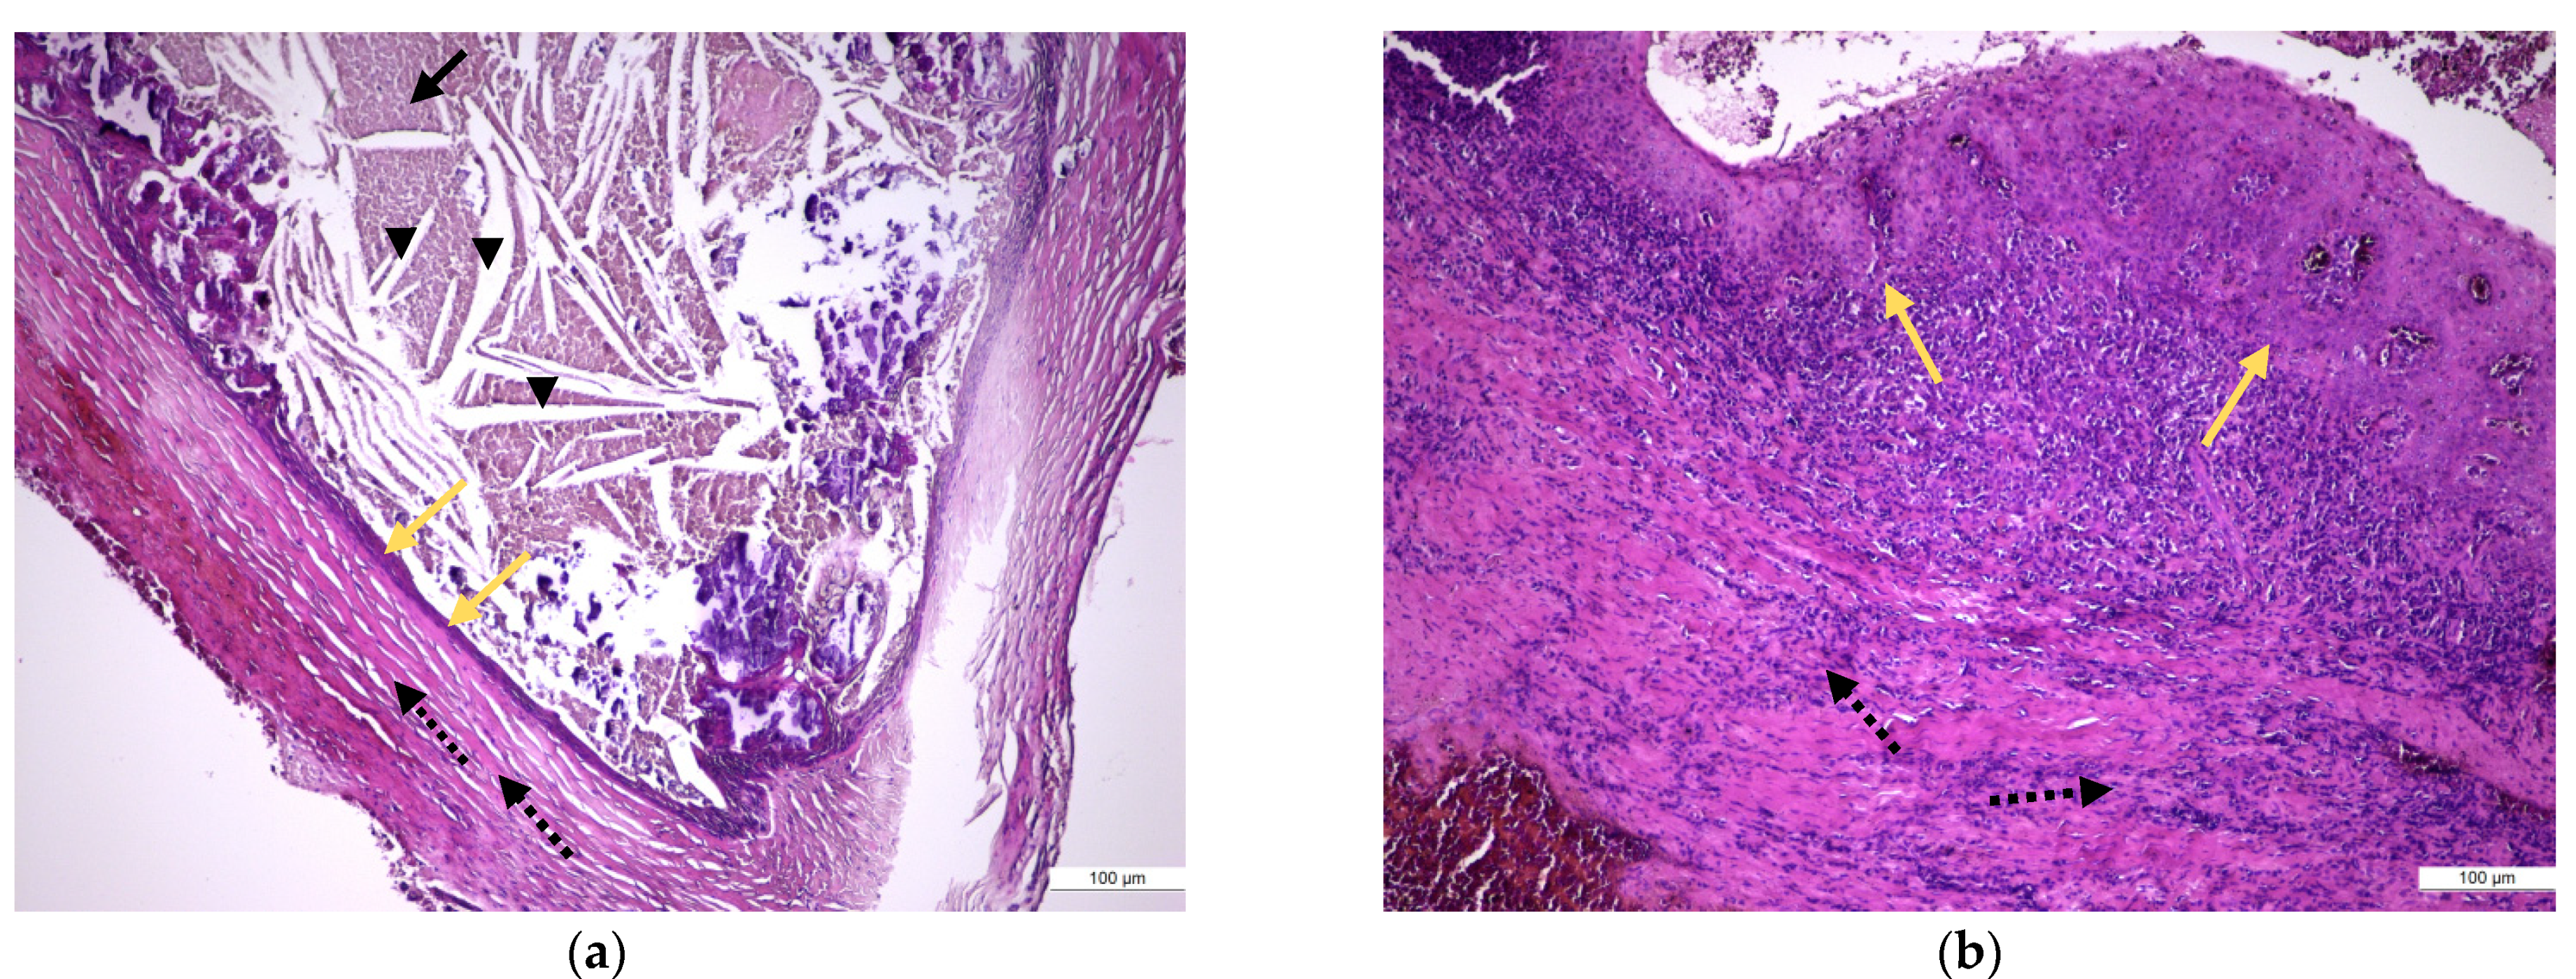

In samples of periapical granuloma in their early stages, the standard staining with hematoxylin and eosin revealed a newly formed fibrovascular tissue (granulation tissue) made up of capillaries and thin collagen fibrils that was infiltrated with a variable proportion of mixed inflammatory cells, mainly lymphocytes, but also plasma cells, macrophages, and multinucleated giant cells (Figure 4a,b). In long-standing periapical granulomas, the number of newly formed blood vessels was reduced, but thick collagen fibers were identified, and the inflammatory infiltrate was very well represented (Figure 4c). The periapical cysts showed a lumen, an inner epithelial lining made up of a stratified squamous epithelium and a fibrous outer capsule, that was infiltrated by variable mixed inflammatory cells (Figure 5a,b).

Figure 4. Histopathological features of periapical granuloma: (a) the early stage revealed a granulation (fibrovascular) tissue infiltrated by a heavy collection of chronic (mononuclear) inflammatory cells (black arrow head) but also few neutrophils (red arrow). There are numerous newly formed small blood vessels (yellow arrow) and thin, immature collagen in the background as well as numerous lymphocytes and plasma cells (HE staining, ×400); (b) the mature stage: granulation (fibrovascular) tissue infiltrated by a collection of chronic (mononuclear) inflammatory cells. There are numerous newly formed small blood vessels and fibrils of collagen in the background as well as numerous lymphocytes and plasma cells but also spindle shape fibroblasts, macrophages (histiocytes), and multinucleated giant cells (yellow arrow) (HE staining, ×100); (c) old stage: large sheets of inflammatory mononuclear cells included into heavy stromal fibrosis (black arrows) (HE staining, ×200).

Figure 5. Histopathological features of periapical cyst: (a) low-power view of a large periapical cyst with a distended lumen that is lined by a non-keratinized stratified squamous epithelium (orange arrow) and is filled with an amorphous eosinophilic material (black arrow head), representing a coagulated fluid high in proteins but also with many cholesterol clefts. The cyst outer wall is thick and is made of fibrous conjunctive tissue (interrupted line arrow) containing a diffuse infiltration of inflammatory mononuclear cells (HE staining, ×10); (b) high-power view of the epithelial lining (orange arrow) but also of the outer fibrous wall that showed a heavy infiltrate with mononuclear inflammatory cells (interrupted line arrow) (HE staining, ×100).